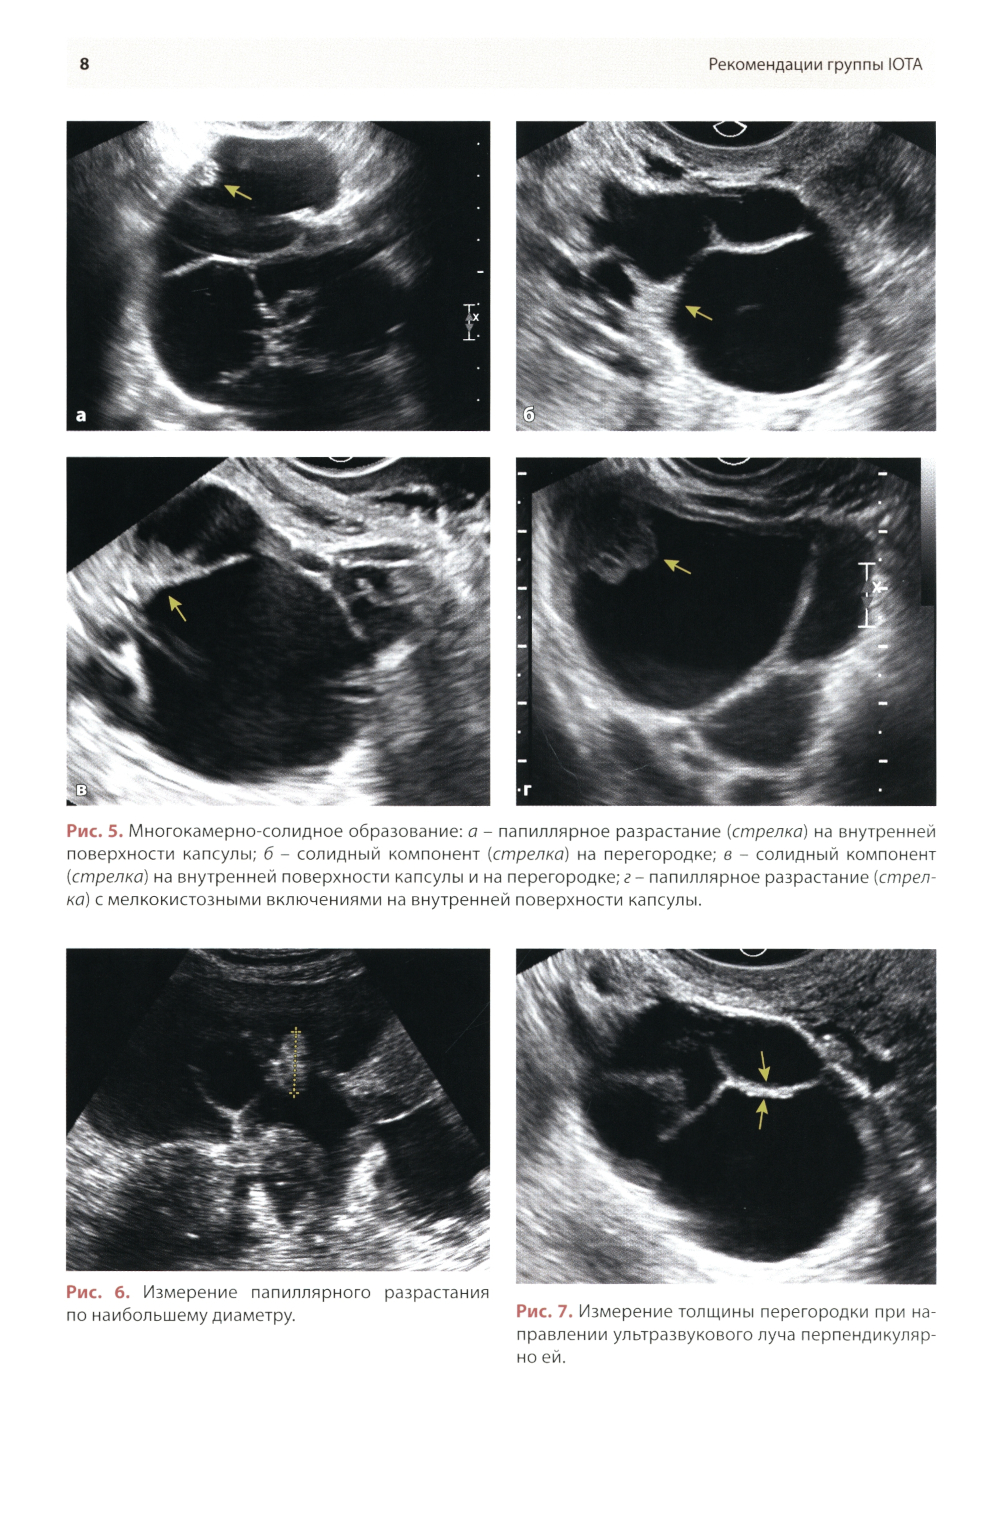

Методические рекомендации по стандартизации ультразвукового исследования с целью своевременной диагностики опухолевого процесса. Книга также включает вопросы дифференциальной диагностики физиологических изменений яичников, опухолевидных и опухолевых заболеваний и маршрутизации пациенток. Утверждено в качестве методических рекомендаций для проведения циклов первичной переподготовки врачей по ультразвуковой диагностике, тематического усовершенствования «Ультразвуковая диагностика в гинекологии», общего усовершенствования, ординаторов и аспирантов, проходящих обучение по направлению «Ультразвуковая диагностика, акушерство и гинекология».| Издательство | МЕДпресс-информ |